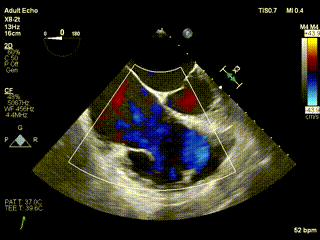

2021年12月24日,復(fù)旦大學(xué)附屬中山醫(yī)院葛均波院士團隊成功應(yīng)用LuX-Valve Plus為一例極重度三尖瓣反流(TR)合并房顫、房缺的患者完成了經(jīng)血管三尖瓣置換術(shù),這是在前基礎(chǔ)上,本周完成的第三例經(jīng)血管三尖瓣置換手術(shù),葛均波院士、周達(dá)新教授等與心外科魏來教授、賴顥教授,心超室的潘翠珍教授、李偉教授及麻醉科的郭克芳教授共同完成了本周手術(shù),均獲得圓滿成功!患者術(shù)后超聲顯示無TR,臨床癥狀明顯改善。本周手術(shù)的成功也為LuX-Valve Plus救治性臨床研究添上了濃墨重彩的一筆。

三例患者入院后,葛均波院士團隊周達(dá)新教授、潘文志教授、張源博士、陳莎莎博士及心超室的潘翠珍教授、李偉教授對患者的情況進行詳細(xì)評估和討論,最終決定為三例患者選擇LuX-Valve Plus40mm、50mm和50mm型號的瓣膜進行手術(shù)治療。手術(shù)后即刻拔除氣管插管,術(shù)后患者三尖瓣反流癥狀得到顯著改善,復(fù)查心超結(jié)果顯示人工三尖瓣瓣膜支架固定穩(wěn)定,瓣葉關(guān)閉形態(tài)未見異常,未見明顯反流。